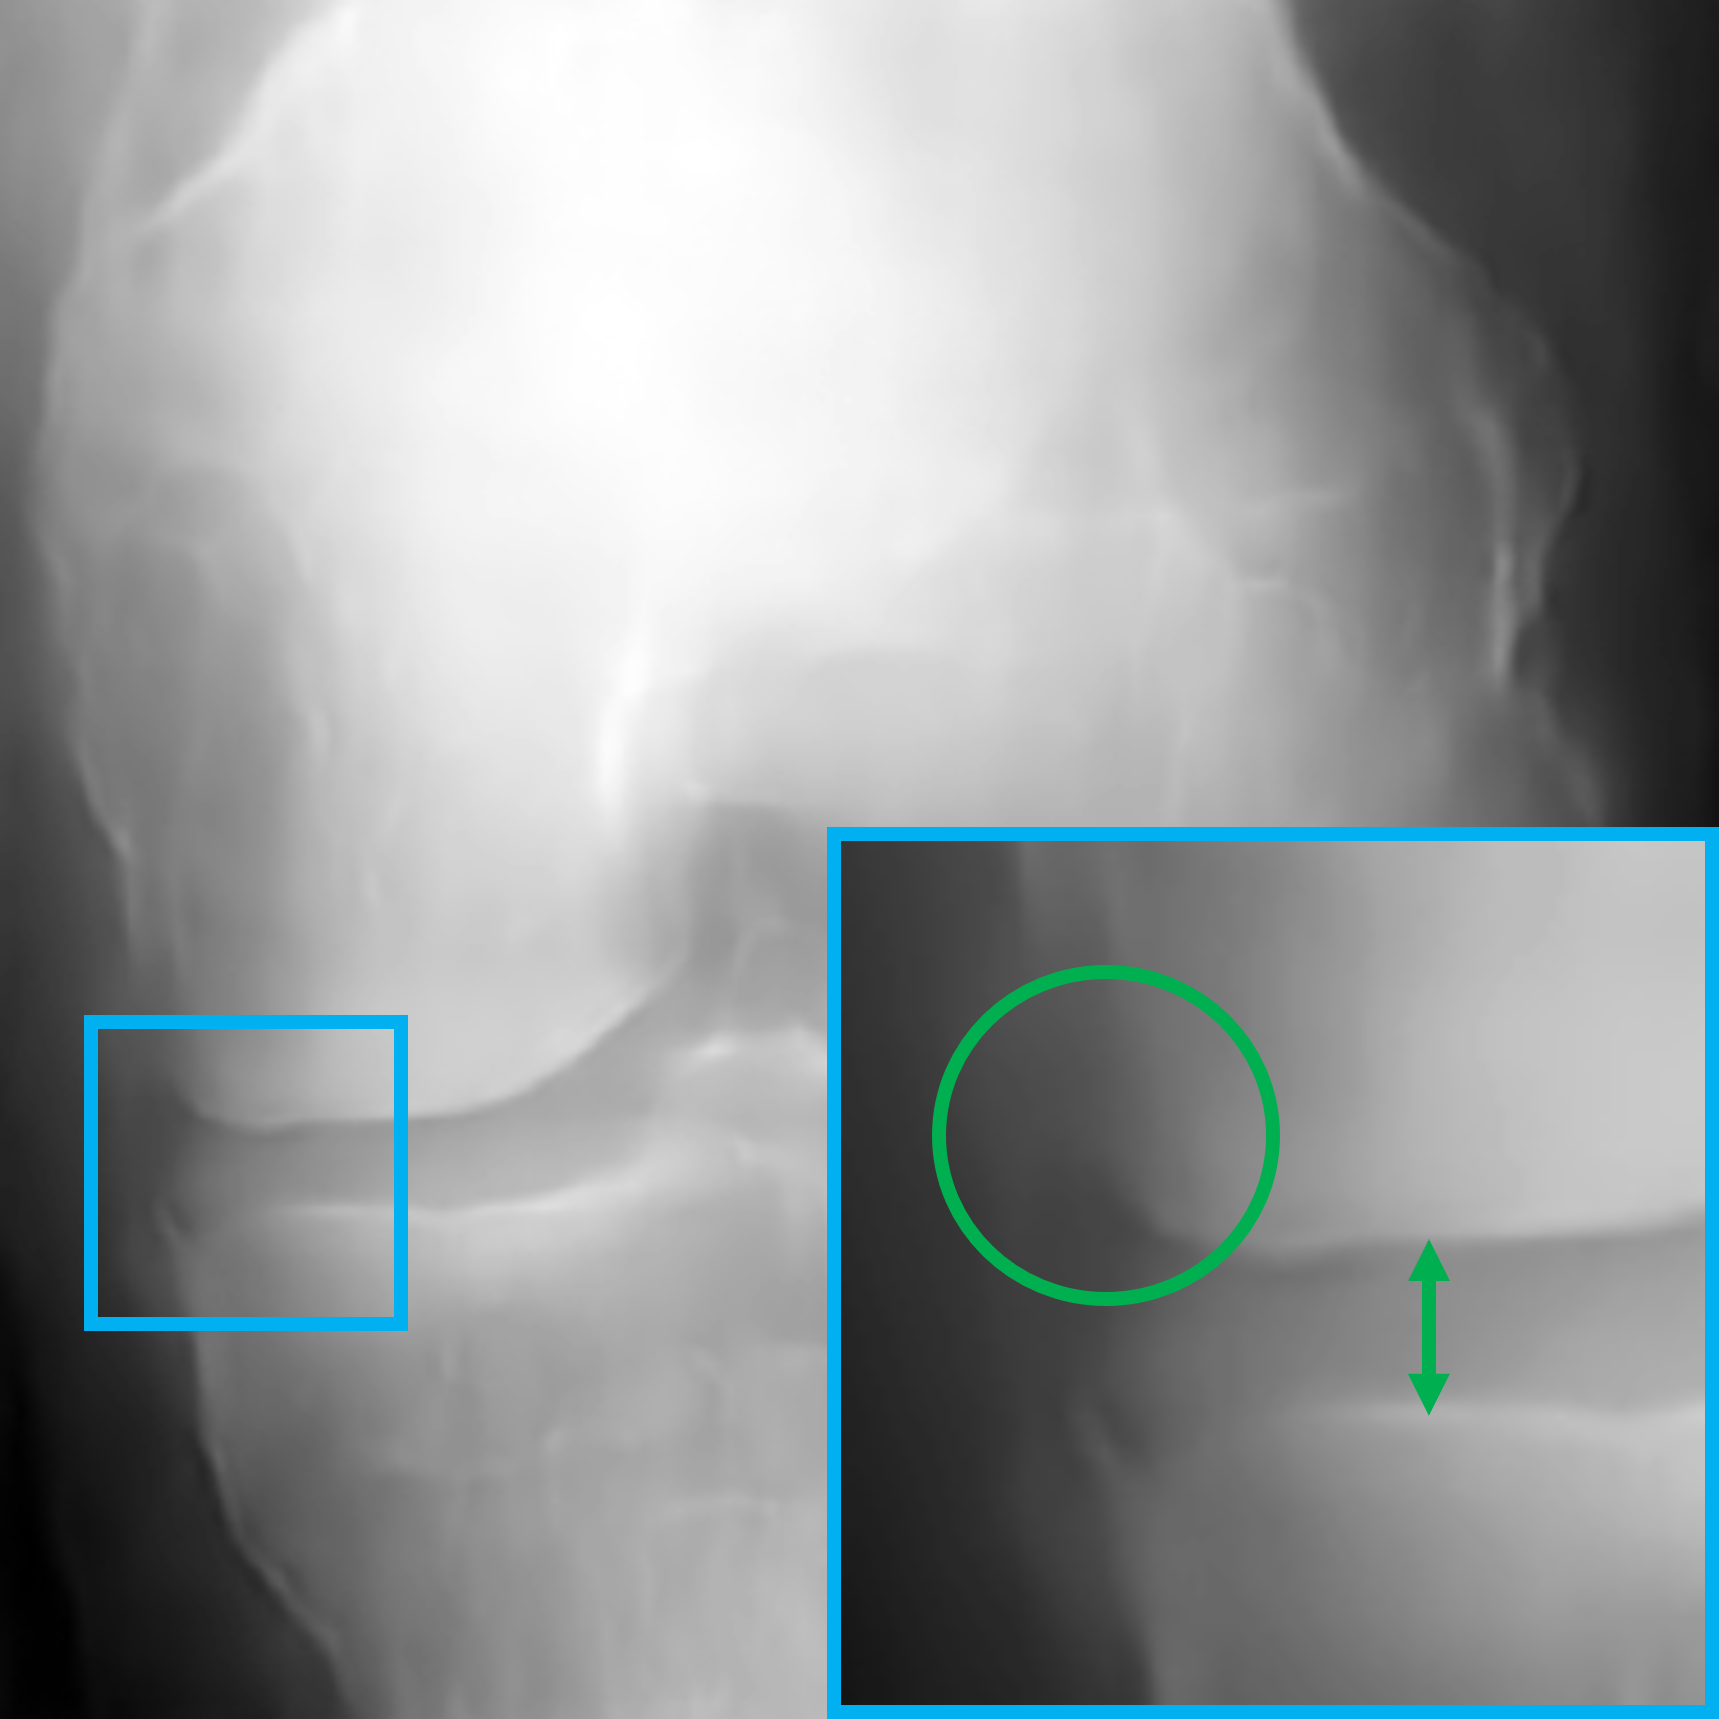

V-B Visualization of the feature vectors

To provide a more intuitive understanding of the proposed key feature exchange mechanism, we visualized the original inputs and their key-exchanged counterparts, as shown in Fig. 4. Specifically, X1subscript𝑋1X_{1}italic_X start_POSTSUBSCRIPT 1 end_POSTSUBSCRIPT (Fig. 4a), a KL-0 healthy knee X-ray, is contrasted with its key-exchanged output X1superscriptsubscript𝑋1X_{1}^{\prime}italic_X start_POSTSUBSCRIPT 1 end_POSTSUBSCRIPT start_POSTSUPERSCRIPT ′ end_POSTSUPERSCRIPT (Fig. 4b), while X2subscript𝑋2X_{2}italic_X start_POSTSUBSCRIPT 2 end_POSTSUBSCRIPT (Fig. 4c), a KL-2 osteoarthritic knee X-ray, is compared with X2superscriptsubscript𝑋2X_{2}^{\prime}italic_X start_POSTSUBSCRIPT 2 end_POSTSUBSCRIPT start_POSTSUPERSCRIPT ′ end_POSTSUPERSCRIPT (Fig. 4d). In X1subscriptsuperscript𝑋1X^{\prime}_{1}italic_X start_POSTSUPERSCRIPT ′ end_POSTSUPERSCRIPT start_POSTSUBSCRIPT 1 end_POSTSUBSCRIPT, pathological features associated with KL-2, JSN and osteophytes, are successfully introduced, while in X2subscriptsuperscript𝑋2X^{\prime}_{2}italic_X start_POSTSUPERSCRIPT ′ end_POSTSUPERSCRIPT start_POSTSUBSCRIPT 2 end_POSTSUBSCRIPT, these features are removed, restoring the joint space to resemble a healthy knee. It is noteworthy that, both X1subscriptsuperscript𝑋1X^{\prime}_{1}italic_X start_POSTSUPERSCRIPT ′ end_POSTSUPERSCRIPT start_POSTSUBSCRIPT 1 end_POSTSUBSCRIPT and X2subscriptsuperscript𝑋2X^{\prime}_{2}italic_X start_POSTSUPERSCRIPT ′ end_POSTSUPERSCRIPT start_POSTSUBSCRIPT 2 end_POSTSUBSCRIPT preserve the structural integrity and background details of the original images, demonstrating the model’s ability to selectively extract and modify key features without compromising realism. These visual results validate the effectiveness of our proposed global approach in separating key and non-key features, ensuring that the generated outputs are both diverse and valid. More details about the clinical validation will be discussed in Section V-E.

Refer to caption

(a) Original input X1subscript𝑋1X_{1}italic_X start_POSTSUBSCRIPT 1 end_POSTSUBSCRIPT (KL-0)

(b) key-exchanged output X1superscriptsubscript𝑋1X_{1}^{\prime}italic_X start_POSTSUBSCRIPT 1 end_POSTSUBSCRIPT start_POSTSUPERSCRIPT ′ end_POSTSUPERSCRIPT (KL-2)

(c) Original input X2subscript𝑋2X_{2}italic_X start_POSTSUBSCRIPT 2 end_POSTSUBSCRIPT (KL-2)

(d) Key-exchanged output X2superscriptsubscript𝑋2X_{2}^{\prime}italic_X start_POSTSUBSCRIPT 2 end_POSTSUBSCRIPT start_POSTSUPERSCRIPT ′ end_POSTSUPERSCRIPT (KL-0)

Figure 4: Highlighted illustration of the original inputs and key-exchanged outputs. The green and red colours represent the absence and presence of symptoms for osteophytes and JSN, respectively. The circles and arrows represent the possible positions of the osteophytes and JSN modification, respectively.